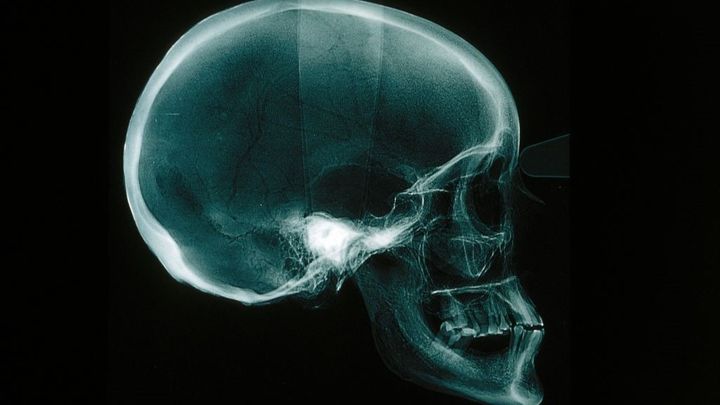

J1アビスパ福岡GK永石拓海が28日に自身のInstagramを更新し、公開した自身のレントゲン写真が話題になっている。

公開された写真は永石の顔面をレントゲンで写した写真であり、合計7カ所の頬骨上顎骨複合骨折を負ったものだった。

鼻骨周辺から長いヒビが入っており、なんとも痛々しい。

福岡は28日に今月9日に開催されたJ1第36節セレッソ大阪戦で永石が頬骨上顎骨複合体骨折を負ったと発表していた。